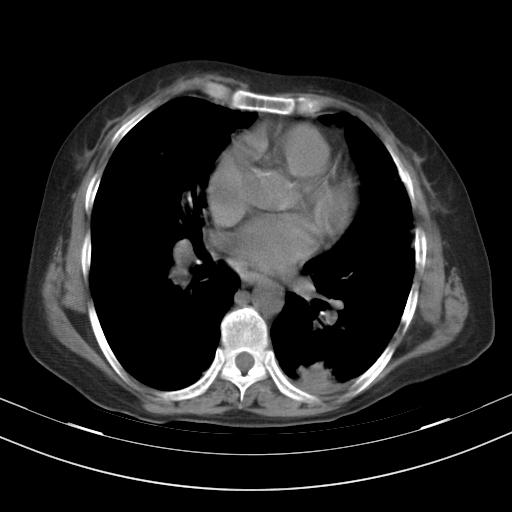

老年女性,嗜睡3天,意识模糊。轻咳,无发热。

两肺慢支炎伴感染,左侧胸腔积液。纵膈及双侧肺门淋巴结肿大建议复查。

1)两肺感染性病变;建议抗炎治疗后复查。2)纵隔淋巴结肿大。3)左侧胸腔积液。